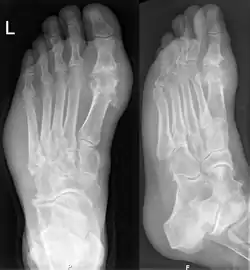

![]() Dna moczanowa w stopie | |

Dnę można diagnozować i leczyć bez dalszego badania u osób cierpiących na hiperurykemię i klasyczną podagrę, należy jednak przeprowadzać analizę mazi stawowej w przypadku wątpliwości co do diagnozy[2]. Zdjęcia rentgenowskie, choć przydatne do rozpoznawania dny przewlekłej, mają niewielkie zastosowanie przy ostrych atakach[7].